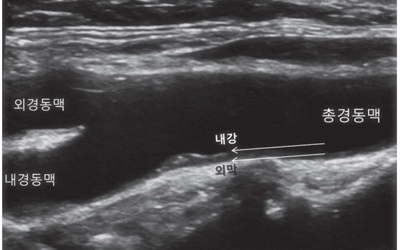

경동맥 초음파 검사는 목 부위에 위치한 경동맥의 상태를 실시간으로 확인할 수 있는 비침습적인 검사 방법입니다. 초음파를 이용하여 혈관 벽의 두께, 혈액의 흐름, 혈관 내 플라크(혈전)의 존재 여부 등을 파악할 수 있습니다. 마치 도로 위에 설치된 CCTV처럼, 혈관 속 상황을 안전하게 들여다보는 것이죠. 검사 과정은 간단하며, 통증이나 불편함이 거의 없어 누구나 부담 없이 받을 수 있습니다.